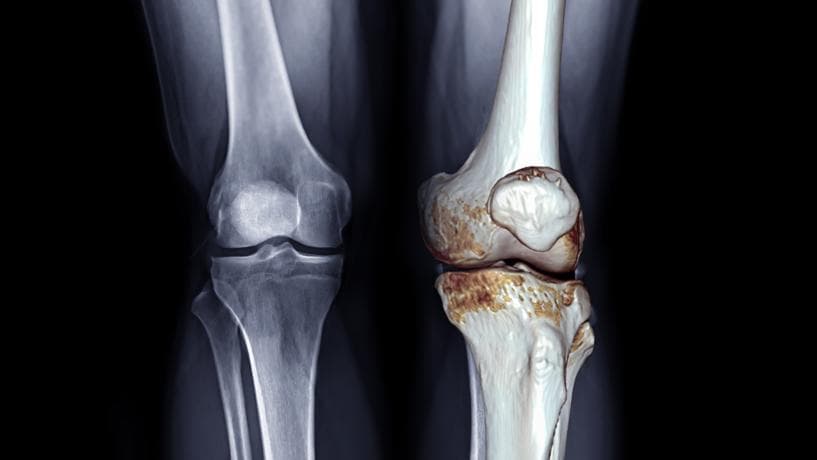

変形性膝関節症とは?

変形性膝関節症は、膝の関節軟骨がすり減ることにより、痛みや腫れ、動かしにくさを引き起こす病気です。現在では1000万人以上の方が膝の不調に悩まされており、特に女性に多く見られる疾患です。

症状の進行

- 初期症状:立ち上がりや歩き始めのときの痛み

- 中期以降:階段の昇り降りが困難になる、正座ができない

- 進行時:安静時でも膝の痛みや腫れを感じるようになる